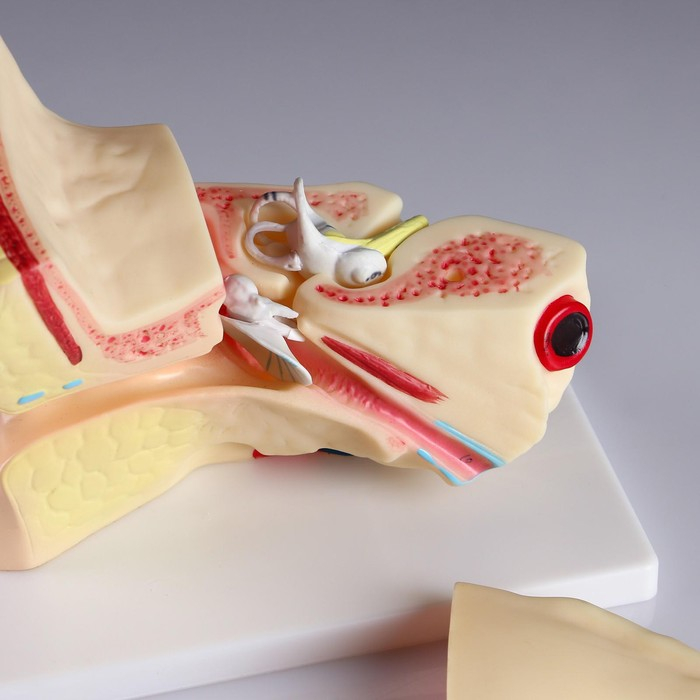

Анатомические модели